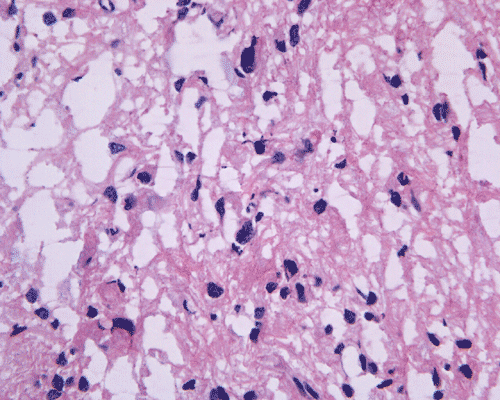

Panel A is T1-weighted post contrast MR image, Panel B is a SPGR T1-weighted post contrast MR image and Panel C is FSE T2-weighted image. Panel D and E are taken from cytologic preparation from intraoperative consultation. Panel F to H are taken from frozen sections. Panel I to L are taken from paraffin section.

Pathology of the case: A small specimen was obtained by endoscopic biopsy. The specimen cannot be smear out after being squashed and remain as several, large, stellate-shaped cohesive clumps (Panel D). The edges of these clumps are relatively thin and allows better observations. The nuclei do not appear to be pleomorphic. Many elongated cytoplasmic processes can be seen (Panel E) and are suggest a glial nature of these cells. The lesion gives a spongy appearance on low-magnification (Panel F). On medium-magnification, there are some clustering of nuclei (Panel G). On high-magnification, the nuclei appear hyperchromatic and pointy but no substantial pleomorphism, prominent nucleoli, or mitotic figure. Some bluish, mucoid material is identified in some microcysts (Ú in Panel H).

There is no endothelial proliferation or necrosis. An  intraoperative diagnosis of glial neoplasm was made. The lesion was entirely resected. On paraffin section, the lesion has a hypocellular background decorated by many small microcysts, often in clusters, that contain mucoid material and small cluster of nuclei that resemble bundles of flowers (Panel I and J).  The nuclei are bland. There was no mitosis, endothelial proliferation or necrosis (Panel K and L).